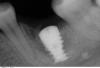

SashaDoc Опубликовано 23 июля, 2013 Поделиться Опубликовано 23 июля, 2013 Коллеги, пришла пациентка, имплант в поз 36, ставила 4 мес назад в другом городе. На этап фдм. По снимку ситуация выглядит следующим образом. ФДМ пока не стал ставить. Резорбция? Периимплантит? Или нет еще интеграции? Признаков воспаления нет. Ссылка на комментарий

Mane Опубликовано 23 июля, 2013 Поделиться Опубликовано 23 июля, 2013 Все там в порядке. Ставьте формирователь смело. Скорее всего там не помешает сст! 1 Ссылка на комментарий

АнтонТЛТ Опубликовано 23 июля, 2013 Поделиться Опубликовано 23 июля, 2013 +1Проверьте на нагрузку, и ставьте формирователь. Ссылка на комментарий